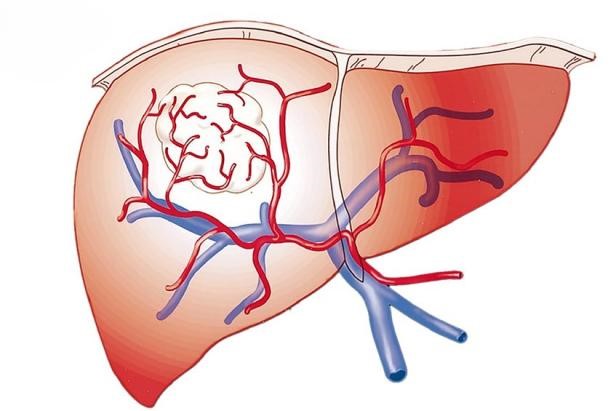

Nhu mô gan lành được cấp máu chủ yếu (80%) từ hệ tĩnh mạch cửa và 20% được cấp bởi động mạch gan. Ngược lại, tổ chức khối Ung thư biểu mô tế bào gan (HCC-Hepatocellular Carcinoma) được cấp máu chủ yếu từ hệ thống động mạch (80%) bao gồm hệ động mạch gan và hệ động mạch ngoài gan.

Hình 2: Nguồn cấp máu nuôi gan bình thường (a) và khối ung thư gan (b)

Hoá chất bơm qua đường động mạch gan sẽ vào trực tiếp khối u, trong khi phần gan lành được nuôi dưỡng bởi nguồn tĩnh mạch vẫn phát triển bình thường. Điều này cũng cho phép đưa được nhiều hoá chất tiêu diệt tế bào u hơn vào trong khối u.